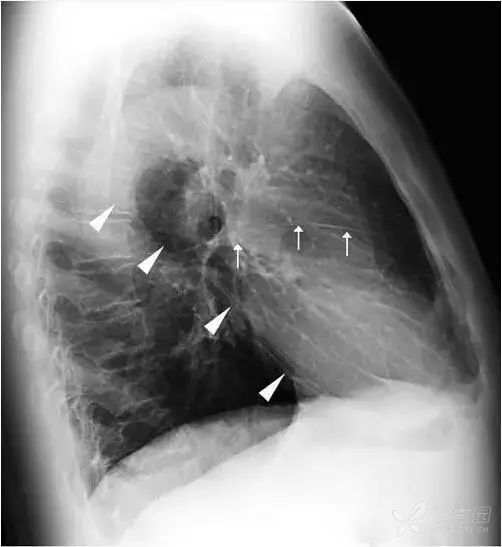

正位胸片上无法看到两肺斜裂。侧位胸片常可见两肺的斜裂(图12)。侧位片也可见水平裂(图12),起自斜裂中点附近,向前水平或稍向下达前胸壁。

图12 三角箭标示两肺斜裂,呈细线状,右肺斜裂起自第4胸椎位置,向前下斜行达横膈前部距前肋膈角约2~3 cm。左肺斜裂起点稍高于右肺,两肺的斜裂在侧位胸片上大致重合。白色箭头标示水平裂,起自斜裂中点附近,向前水平或稍向下达前胸壁 。